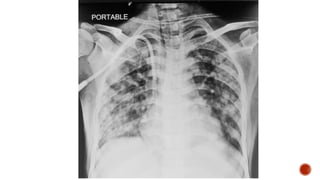

Frontal chest radiograph shows few ill defined patchy opacities in both the lung

fields, few of them showing cavitatory changes. TCC seen in situ.

Compared to the previous radiograph there is reduction in the number of opacities

with cavitatory changes.